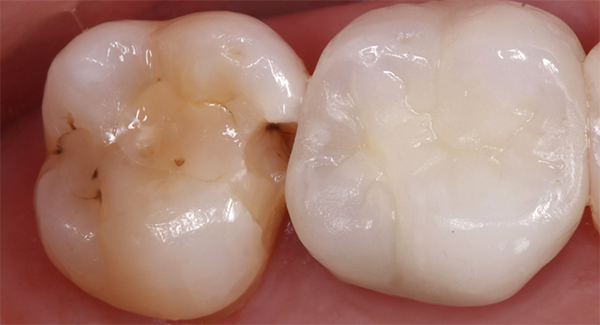

Fig 4. Preoperative visual.

Figure 4

When performing multiple adjacent restorations, preliminary assessments must be made to achieve a successful contact. First, a dental professional must use visual (Figure 4) and radiographic analysis (Figure 5) to establish the location and extent of the caries and assess the adjacent teeth for normal anatomy. Protection of the adjacent teeth during preparation to preserve anatomy and maintain a smooth surface must be ensured, which will help in reducing plaque accumulation. Afterwards, teeth should be prepared with an efficient sequence, and the type and location of matrices should be determined. Next, sequences of steps should be established if adjacent contacts must be restored to ensure that successful anatomic contours are reconstructed. Then a pre-etch technique should be used to optimize the seal of the occlusal portion of the restoration. An adhesive seal of the resin to the tooth structure may be created with a reliable adhesive system, and sectional matrices can be used to form tighter contacts in posterior resin restorations.